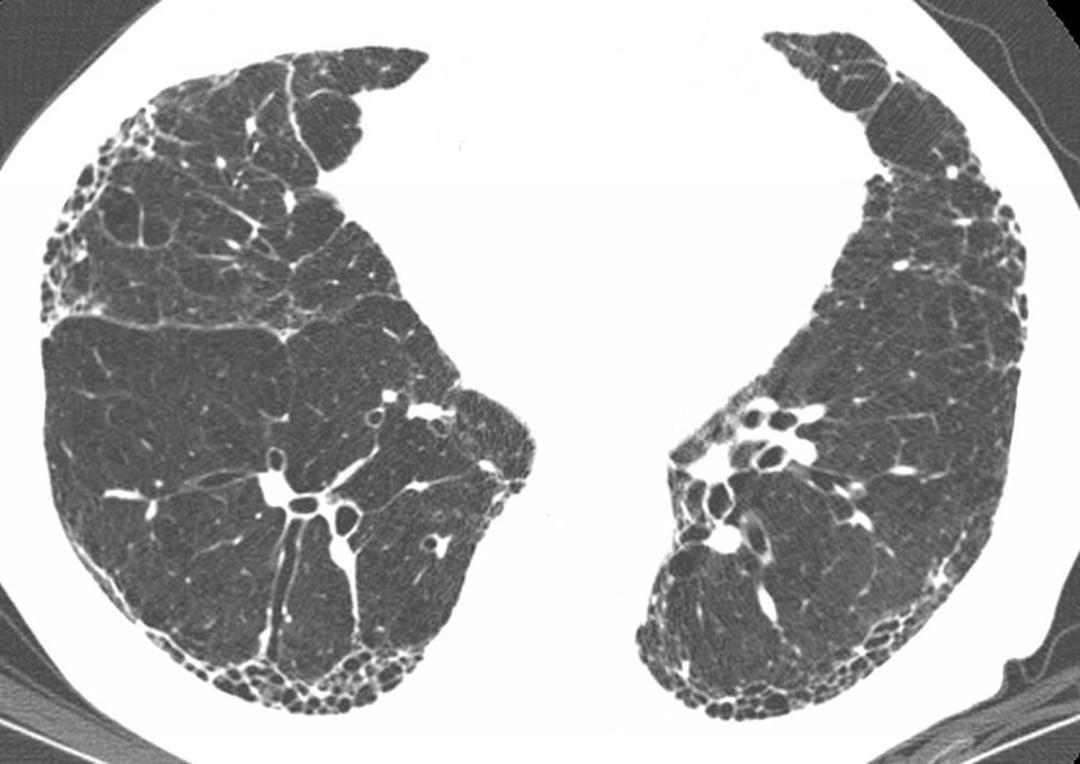

警惕无症状晚期肺癌,两肺到处是肿瘤患者却毫无感觉,诊断即晚期

肺是一个不敏感的器

不知不觉就得了晚期肺癌,有人甚至觉得自己很健康,其实早有预兆

毫无症状的晚期肺癌

无症状肺癌是如何形成的,很多人完全没有意识到症状,发现时已迟

门诊上经常碰到没有

警惕“无症状”晚期肺癌,有些人转移了还没有意识到,发现已晚

肺癌是毫无争议的癌王